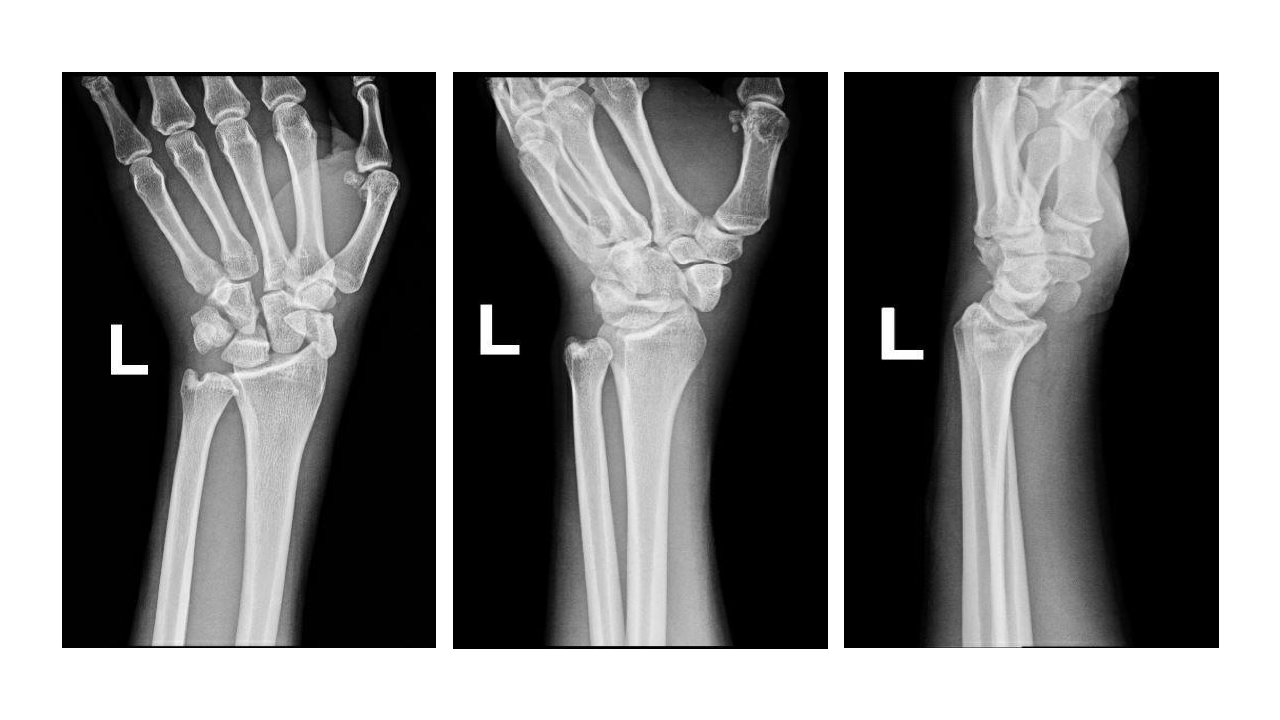

Distal radial and ulnar styloid fracture Image Radius Bone Dislocation distal radius fractures are one of the most common types of bone fractures. Radius and ulnar shaft fractures, also known as adult both bone forearm fractures, are common fractures of the forearm. Fractures of the forearm can occur at different levels: Near the wrist at the farthest (distal) end of the bone, in the middle of the forearm or. Radius Bone Dislocation.